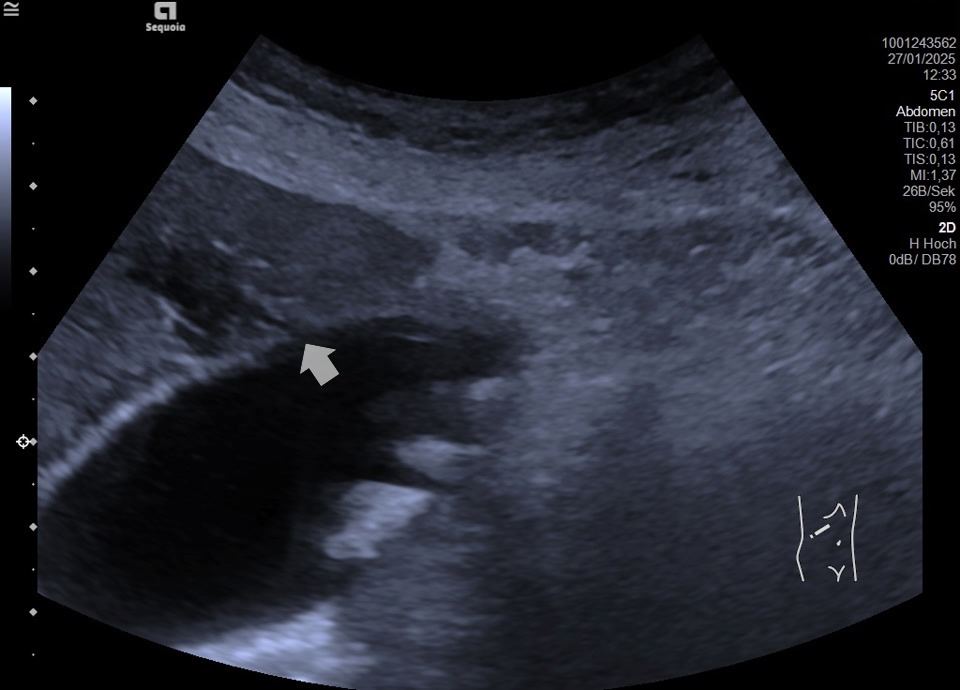

Acute cholecystitis

Akute Cholezystitis (Wand verdickt und geschichtet), zusätzlich Gallenblasenstein im Fundus